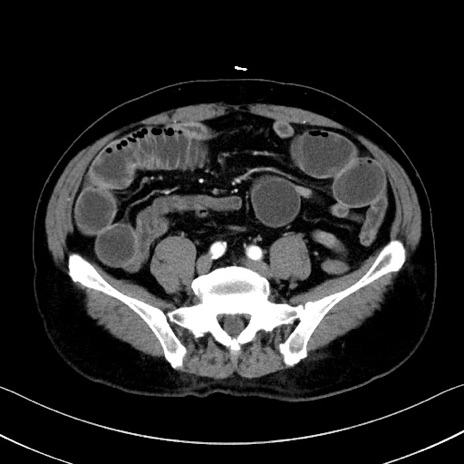

症例35(横断像)

冠状断像

【症例】70歳代 男性

【主訴】腹部膨満、嘔吐

【現病歴】昨日より腹部膨満感出現。本日増悪し、仙痛出現。嘔吐あり、受診。

【既往歴】糖尿病、胆摘後

【身体所見】BP 149/80mmHg、HR 74/min、BT 35.9℃、腹部:膨満、軟、圧痛なし。腸雑音減弱あり。上腹部正中切開瘢痕あり。

【データ】WBC 13500、CRP 1.72